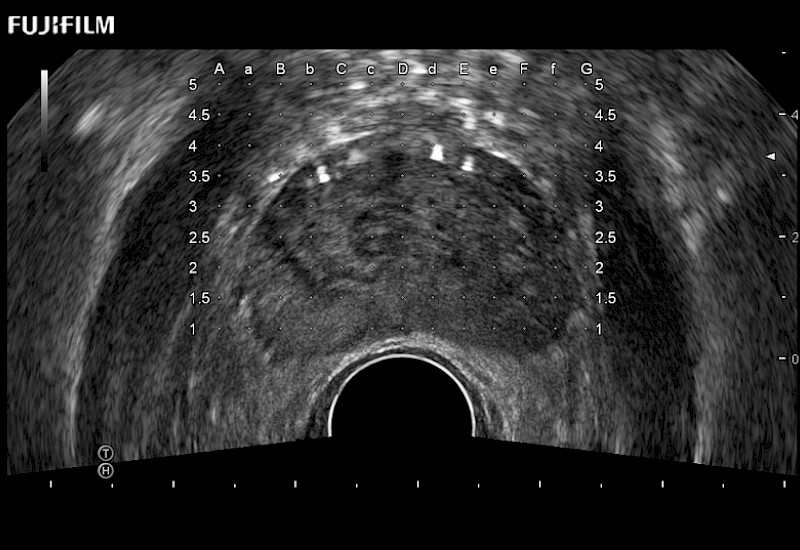

Exclusive 200° FOV end-fire prostate biopsy transducer.

Main Specifications:

Provides real-time imaging of both the sagittal and transverse planes